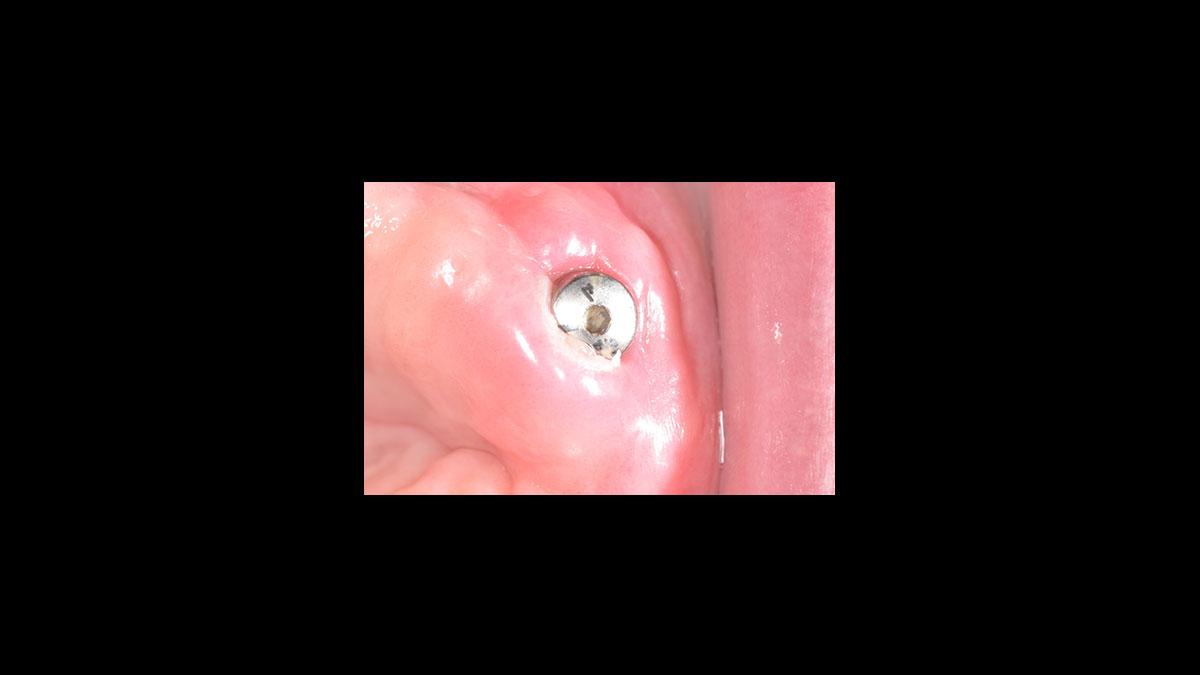

• Descubrimiento del implante

Descubrimiento del implante